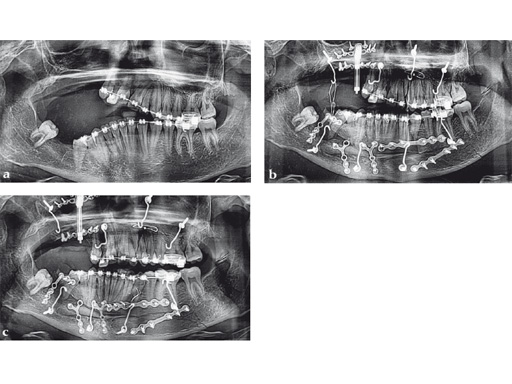

Case 2: Complex congenital deformity with distortion of alveolar processes and dentition, resulting in a 3.5 cm nonocclusion in the right maxillomandibular complex. Occlusion is exclusively controlled through the left second premolar to second molar. Piezosurgery was useful in this case due to complex anatomical deformities resulting in atypical positioning of the inferior alveolar canal on the right side. The cramped confines of dental and bony tissues in the deformed anatomy required an adequate type of osteotomy to do a significant yet controlled skeletal movement to overcome the vertical discrepancy intraorally, without changing the outer projection of the mandibular frame.

Case provided by Nils-Claudius Gellrich, Hannover, Germany